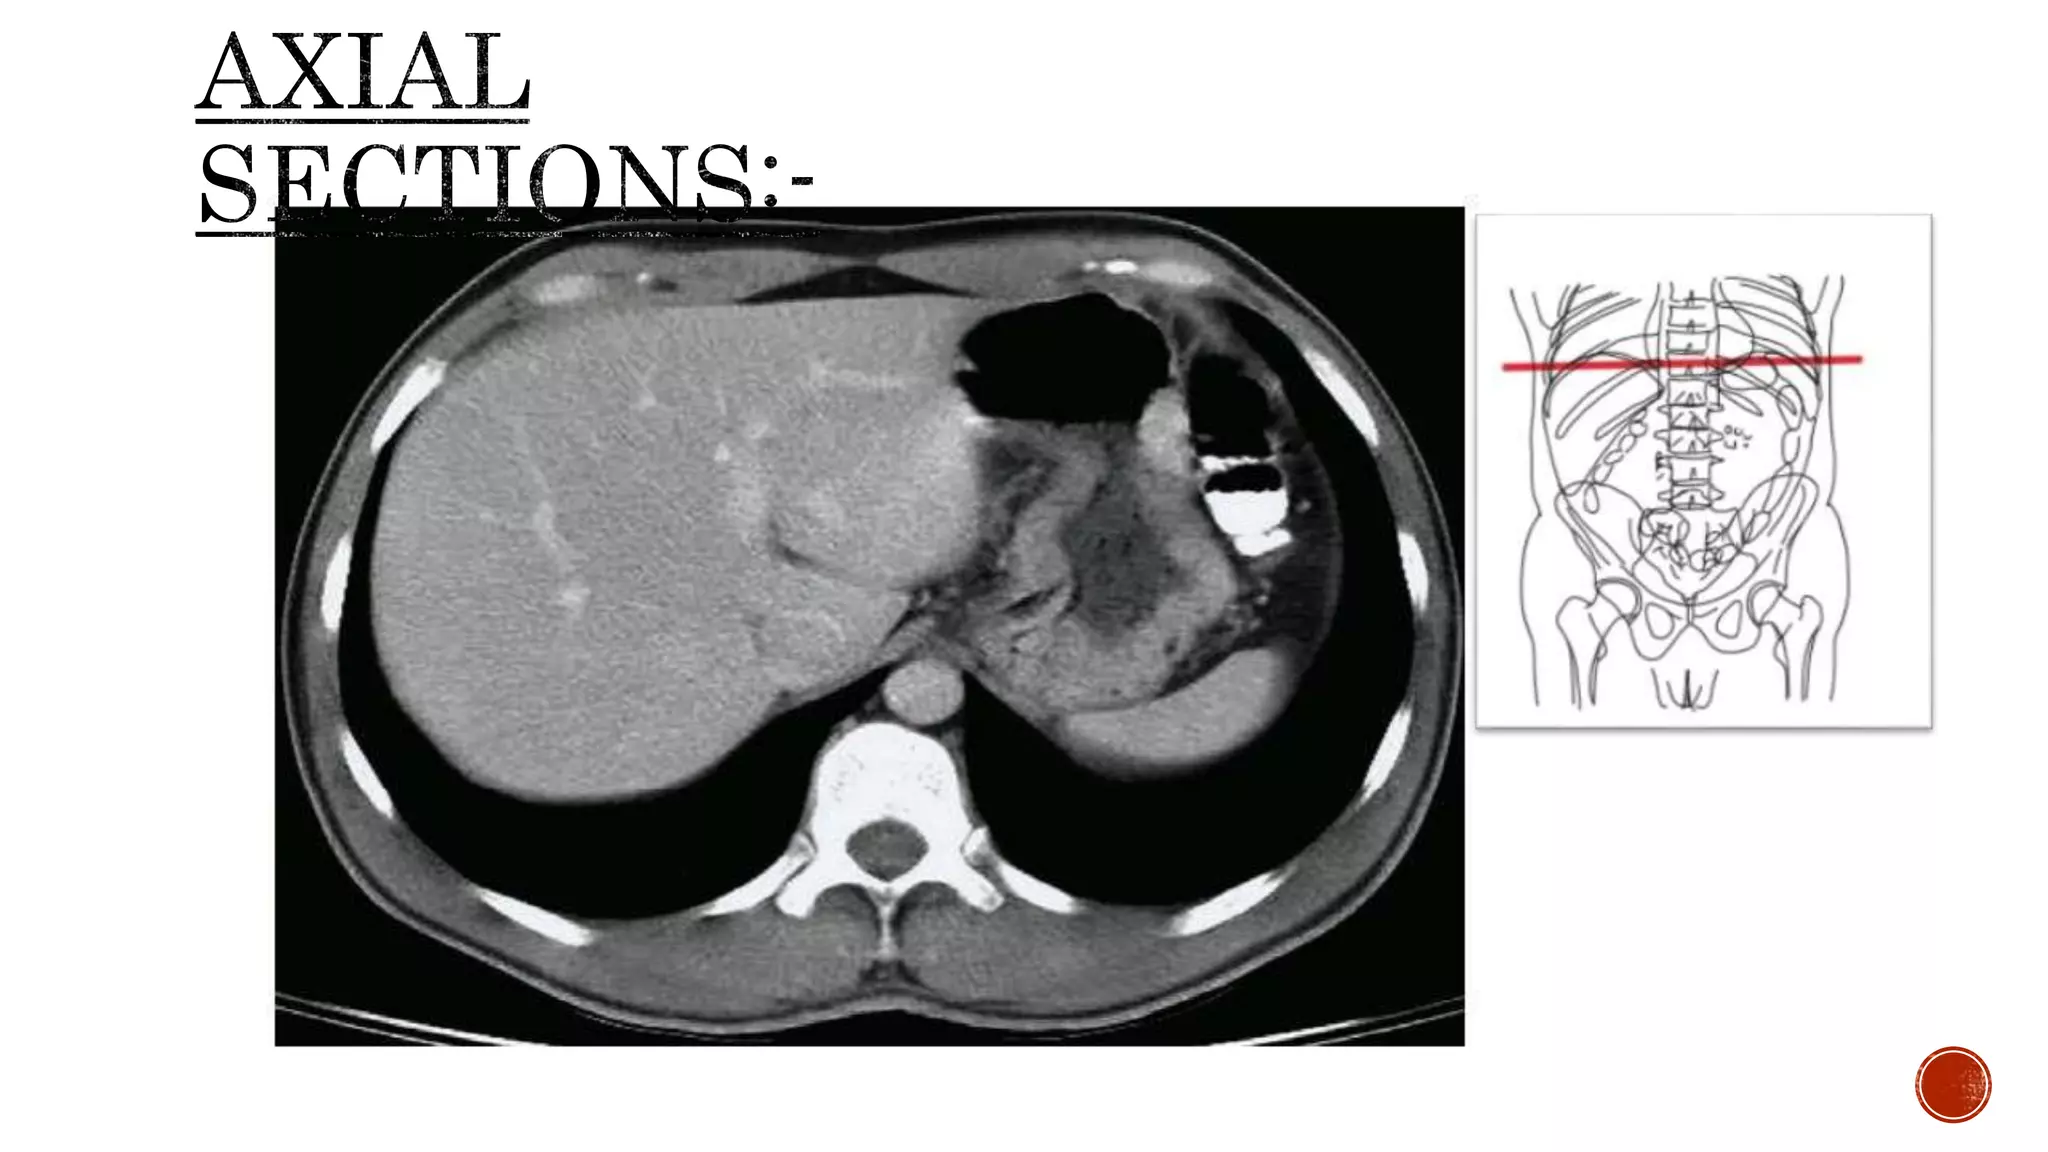

The document describes the anatomy of the abdomen and pelvis region of the human body. It lists over 40 structures and their locations, including major organs like the liver, kidneys, intestines, blood vessels and muscles of the abdominal wall and pelvis. The structures are grouped into sections focusing on different anatomical areas like the abdomen, retroperitoneum, pelvis and gluteal region.